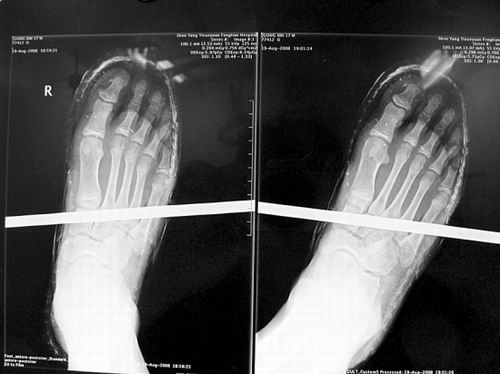

X光片顯示無大礙

事發(fā)時男孩穿著一雙布鞋,骨外二科陳賓醫(yī)生操起剪刀,將布鞋一塊塊剪掉。經(jīng)X光透視,醫(yī)生驚奇地發(fā)現(xiàn):男孩雖然被鋼筋穿透了右腳,但骨頭、大的血管和神經(jīng)都沒受任何傷害!

20日,記者從X光片子上看到,鋼筋避開了男孩腳掌骨頭密集的部位,而是從腳弓處穿過,這個部位基本上以軟組織為主。“真沒想到,太神奇了!”幾名醫(yī)生連聲感嘆,術(shù)中,他們分工合作,小心翼翼地將鋼筋取出,并做了引流、清創(chuàng)、包扎。